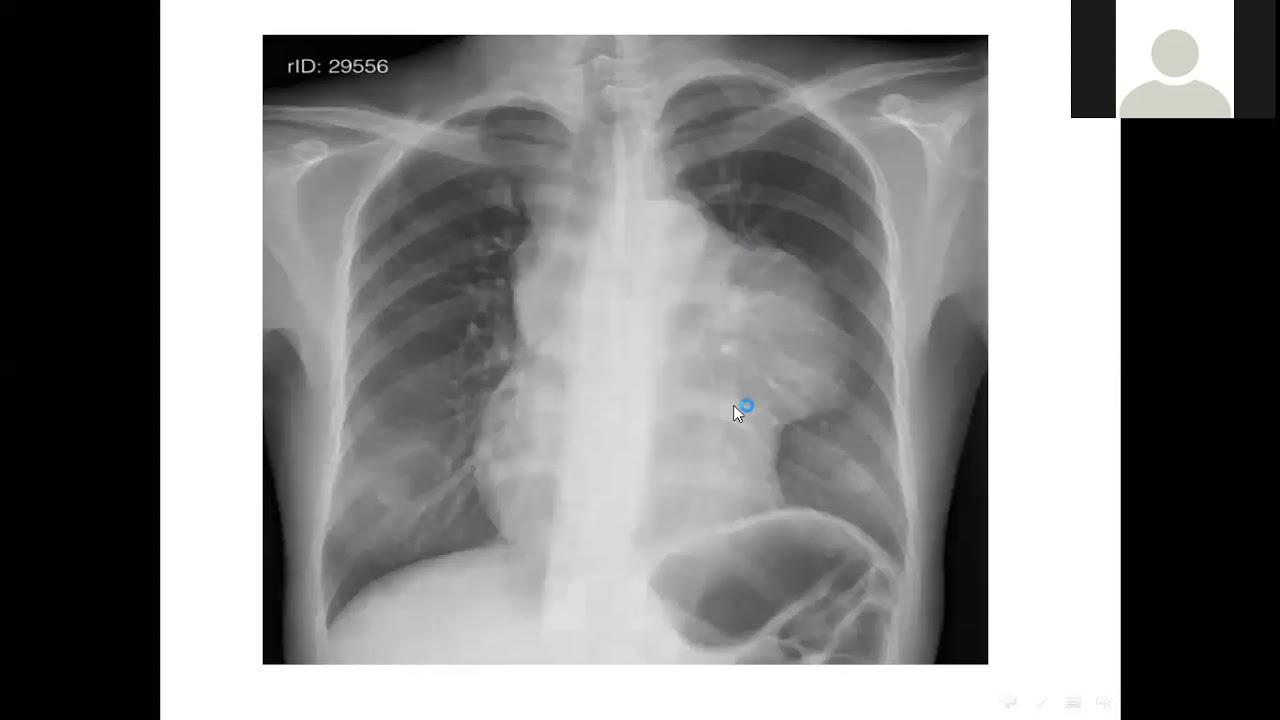

From www.studypool.com

SOLUTION Chest x ray lecture Studypool Chest X Ray Lecture Understand the key concepts of reading a chest radiograph with this. a free medical lecture on chest x ray (cxr) interpretation. — a description of a systematic method for examining a chest x. In fact every radiologst should be an. Chest X Ray Lecture.